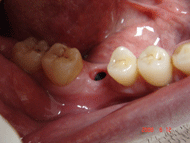

| <症例4> |

| 右下6番パーフォレーションによる骨吸収のため抜歯。両隣在歯がノンカリエスのためインプラントを選択。 |